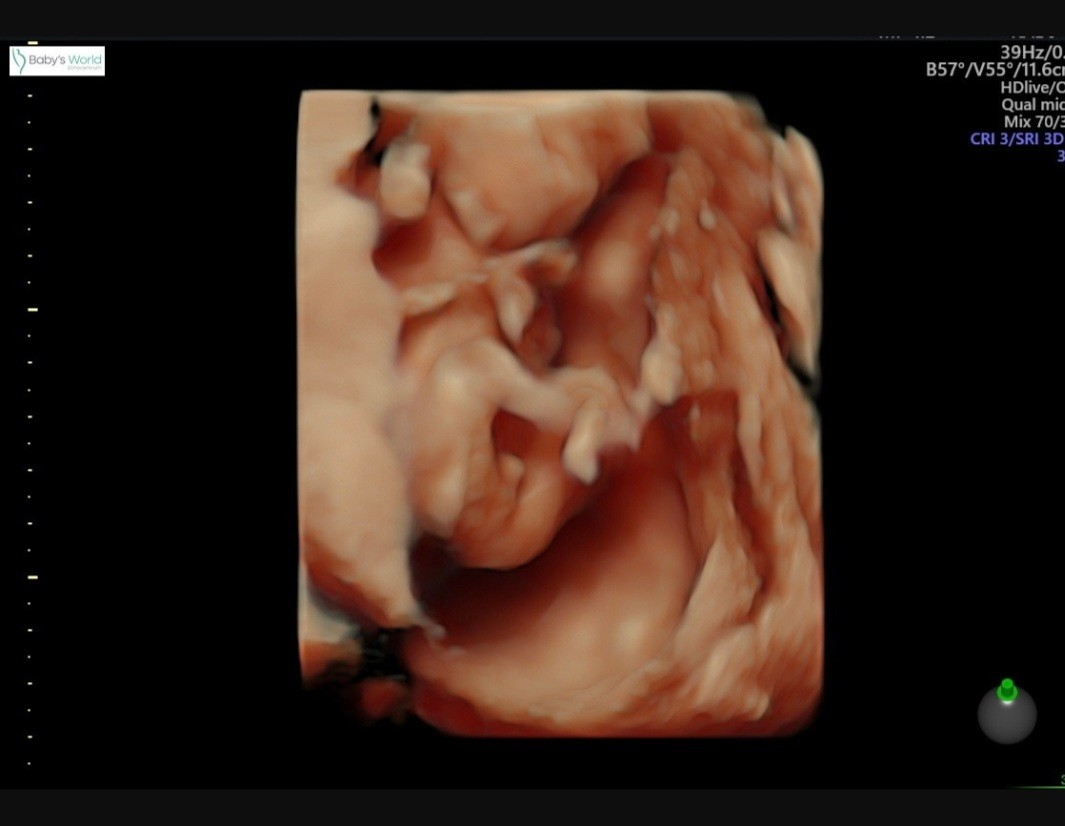

Przesyłam zdjęcie usg z 13. tygodnia

Lekarz mi powiedział, że będę miała dziewczynkę i to są jej narządy...tylko, że powiększone bo tak w tym czasie jest często.

Okazuje się, że zrobił się po dwóch tygodbiach chłopiec. Co myślicie o tym zdjęciu ?